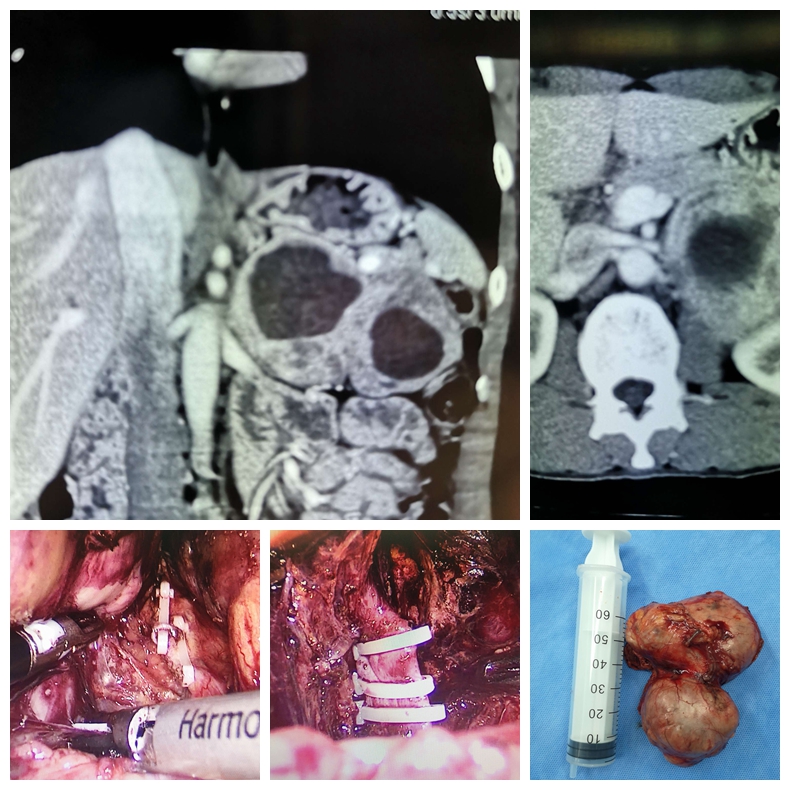

腹腔镜左肾上腺切除术治疗大体积嗜铬细胞瘤的病例

科室积致力于泌尿外科微创技术的创新和优化。在广泛开展腹腔镜肾癌根治术、肾部分切除术、前列腺癌根治术、全膀胱切除术及肾上腺肿瘤切除术等基础上,进一步扩大腹腔镜技术的覆盖范围,开展腹腔镜下腹膜后和盆腔扩大淋巴结清扫术等高难度手术。推动外科微创化与加速康复外科(ERAS)的紧密结合,打造成特色、优势技术,受到广大患者认可。泌尿系统结石疾病的诊治是我科的传统优势项目,保持着省内先进水平。我科应用经皮肾镜技术开展了一些高难度的肾结石手术,如严重脊柱畸形患者的肾结石、孤立肾肾结石、无肾积水的肾结石、马蹄肾肾结石等,而且手术均取得成功。泌尿系肿瘤的发病率逐年升高,其防治任重而道远。我科积极开展复杂性泌尿系肿瘤的诊治,尤其是巨大肾上腺肿瘤、巨大肾肿瘤、孤立肾较大肾癌的保留肾脏手术等。同时积极开展泌尿系肿瘤的防治研究,重点进行泌尿系肿瘤病因学的研究,尤其是寻找膀胱癌、肾癌和前列腺癌相关功能基因,从基因学角度寻找肿瘤特异标记物,提高泌尿系肿瘤早期诊断水平,并为进一步基因治疗提供基础。前列腺增生作为老年男性常见疾病一直以来是我们重点研究的方向和医疗特色之一。随着外科技术的不断进步及新的医疗设备的不断涌现和完善,TURP的金标准地位逐渐受到挑战,如经尿道钬激光前列腺剜除术技术日臻完善,大有取代TURP之势。目前我科已积极开展经尿道钬激光在良性前列腺增生治疗中的应用,取得了良好的治疗效果。我科针对目前男性疾病诊治需求量迅速增加的现状,积极开展男科的特色诊疗,范围包括男子勃起功能障碍、早泄、男性不育症、精索静脉曲张、血精、阴茎硬结症、睾丸附睾疾病、男子生殖系统内分泌疾病等。开科以来典型手术介绍如下: